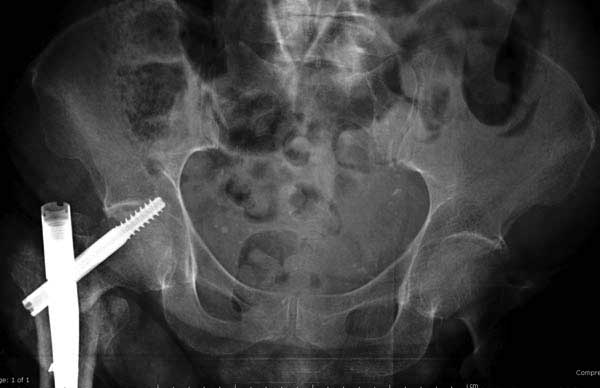

Вторая операция- это фаза сохранения головки бедра. Желательно приложить все усилия и сохранить головку, но, как видно, “фиаско” продолжается. Здесь вместо нейтрализации сил между медиальной и латеральными сторонами была попытка удержать варус. Варус не удержать ни деротационными шурупами о котором говорили и не костными стружками вбитые в шейку, потому что вся нагрузка упирается в головку.

Как отметил Евгений, 95 degree Blade Plate Fixed Angle device  расчитана на восстановление взаимоотношении между головкой и диафизом, а все остальные фиксаторы (Gamma, Afifuxus и др.) работают за счет нагрузки в верхнем полюсе головки. Верхний полюс успели разрушить, и в головке единственное место, который смог бы удержать широкий клинок конструкции, это медиально-низкий сегмент. После установки клинка засчет дистракции можно удлинить конечность на 15мм, а добавленный в дефект ауто-графт закончил бы дело.